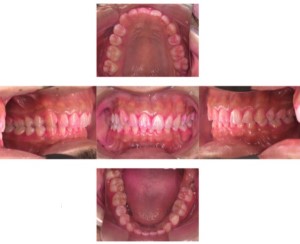

症例

症例1

Before

after

基本情報

年齢・性別 52歳・男性

主訴 主訴:久しぶりの歯医者なので歯石をとってほしい

治療部位:全顎

治療内容 1.歯磨き指導、歯肉縁上の歯石除去

2.歯磨きの確認、指導(磨けるようになるまで)

3.歯磨きの確認、指導、歯肉縁下の歯石除去(SRP)

4.PMTC

5.再評価、歯磨きの確認、指導

治療期間 1日

治療費 合計17,560円

・内訳

1、歯周基本検査・歯磨き指導、縁上スケーリング:1,800円

2、歯周精密検査・SRP(スケーリング・ルートプレーニング)、歯磨き指導:2,130円

3、SRP、歯磨き指導:3回(1,530円×3回)

4、PMTC、全顎再スケーリング、歯磨き指導:5,500円(自費診療)+1,260円

5、再評価(歯周精密検査)、歯磨き指導:2,280円

※PMTC以外、保険診療3割負担

(2023年5月現在現在)

リスク・副作用 ・毎日の歯磨きが不十分だと歯石を除去しても再度歯石がついてしまう

・最初は歯磨きのときに出血してくることがあるが、細菌が減って歯茎が引き締まってくると徐々に出血は落ち着いてくるため痛みがなければ辛抱強く磨いてもらう

・歯周病は時間をかけて静かに進行する病気なので、歯周病を治すにはそれなりに期間がかかる、すぐには治らない

・歯ぐきが引き締まると歯茎が下がり歯間に隙間ができる可能性がある

治療方針 一時的な治癒ではなく、将来的にこの治療が活かされるよう、患者さん自身である程度自己管理ができるようになることを目標とした

特記事項 ふつうのブラシと電動歯ブラシ使用(ブラウン丸型使)

歯間ブラシを1日1回は最低でも使って頂いた

担当者所見 あまり器用な方ではなかったため、決まったところがいつも磨けず奥歯に歯間ブラシがなかなか入れられませんでしたが、歯間ブラシのサイズを変えてみたり、内側から入れてみたりと試行錯誤してなんとかある程度磨けるようになりました。

その結果、出血が100%から7%へ激減することができました。

ただSRPをしただけではここまでの結果は出なかったと思います。

それほど日々のセルフケアが重要だということを再認識しました。

歯周ポケットが残っている部位、出血がある部位に関しては引き続き歯磨きを念入りに行なってもらう。

症例2

歯周病検査(治療前)

歯周病検査(治療後)

レントゲン写真

年齢・性別 41歳・男性

主訴 主訴:歯ぐきから出血する

治療内容 1.歯周ポケット検査、資料取り(レントゲン写真14枚・口腔内写真)、歯磨き指導

2.歯磨き指導チェック、縁上の歯石除去

3.縁下の歯石除去4回

4.再評価(歯周ポケット検査・レントゲン写真14枚・口腔内写真)

5.メインテナンス

治療費 合計:14,160円

内訳(全て保険診療3割負担)

・初診検査、歯磨き指導、縁上の歯石除去:3,630円

・レントゲン写真、縁下の歯石除去①:3,040円

・縁下の歯石除去②:1,530円

・歯磨き指導チェック、縁下の歯石除去③:2,070円

・縁下の歯石除去④:1,530円

・再評価:2,360円

(2022年5月現在現在)